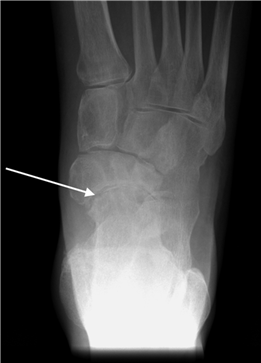

Weight-bearing anteroposterior (AP), lateral, and sesamoid axial radiographs are mandatory. On the AP view, the surgeon measures the Hallux Valgus Angle (HVA, normal < 15°), the Intermetatarsal Angle (IMA, normal < 9°), and the Distal Metatarsal Articular Angle (DMAA). The lateral view is scrutinized for Meary's angle (talo-first metatarsal angle) to identify midfoot collapse, as well as the presence of dorsal osteophytes indicative of hallux rigidus. The sesamoid axial view is critical for assessing the degree of sesamoid subluxation and the integrity of the crista.

Clinical & Radiographic Imaging Archive